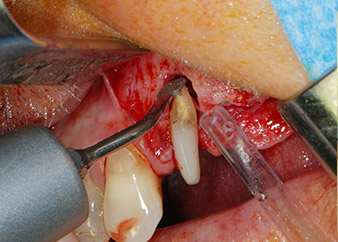

Въпреки това, ние се придържахме към първоначалния си план да запазим и двата зъба като абатмънти за временен мост по време на 6-месечната остеоинтеграция на имплантите. При повторна интервенция, ситуацията трябва да се преразгледа. Първо, в опит да се овладее ендо-перио проблема, останалата повърхност на зъба е внимателно обработена с пиезохирургично оборудване (Piezomed, W&H, използван с накрайник S1 под формата на шпатула, първоначално проектиран за ерозия на латералната синусна стена) (Фиг. 4).

След това апексът се изпилява със същия инструмент, за да се отстрани остатъчната инфектирана апикална тъкан и да се намали възможното допълнително усложнение по кореновите канали (апикоектомия) (Фиг. 5). Ретроградно запълване не е необходимо, защото ортоградното запълване току-що е ревизиран.

Фиг. 4: За да се съхрани зъбът като временен абатмънт, периодонциумът е изпилен с пиезохирургично оборудване...

Фиг 5: ... и букалният апекс на зъб 24 е обработен със същия инструмент (апикоектомия).